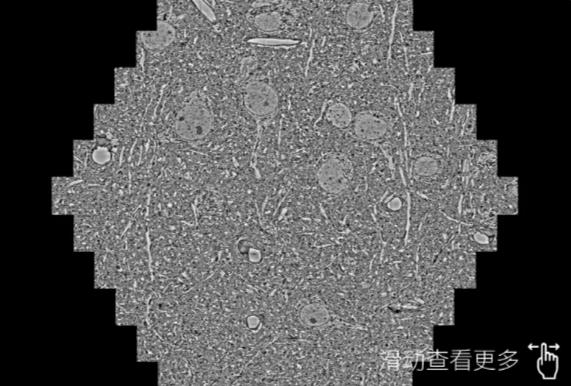

鼠脑切片。左图使用南宁蔡司南宁扫描电镜MultiSEM706对165μmx143pm面积区域成像,耗时仅需1.5秒。右图为鼠脑切片中30μm区域放大效果。样品由芝加哥大学B.Kasthuri提供。

使用蔡司高速南宁扫描电镜MultiSEM对1mm²人脑皮层组织进行高分辨成像,并对其中的各种细胞结构进行三维重构分析。左图展示了2x3mm²组织平面中锥体神经元的三维重构效果。右图显示了局部体积神经元三维重构。图像由哈佛大学chtman实验室提供,渲染图由D. Berger 制作。